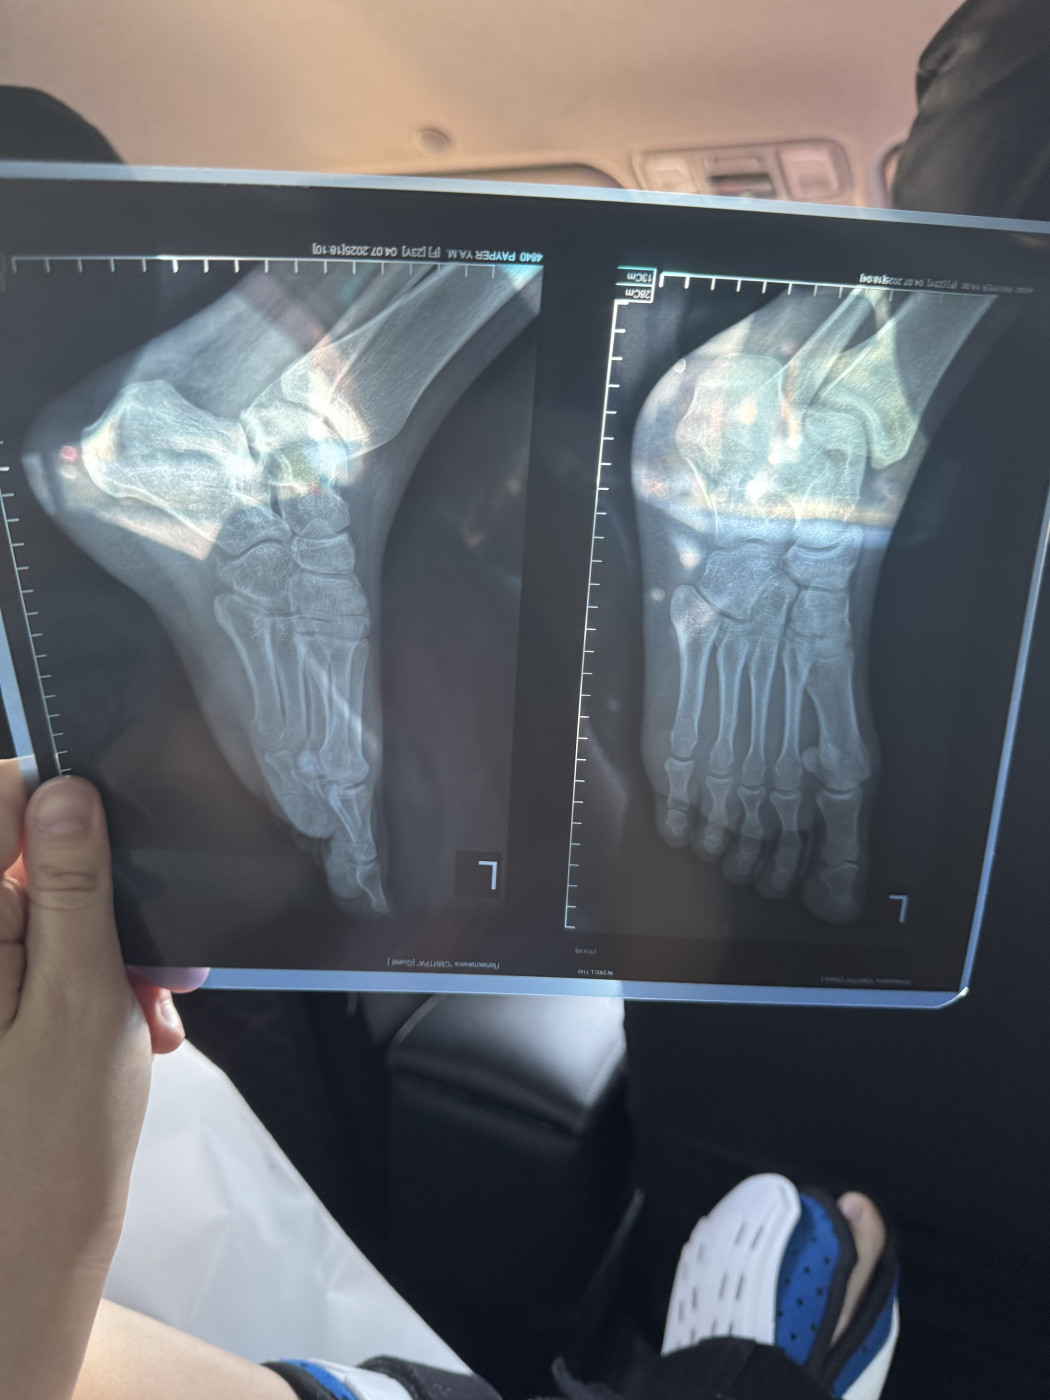

Перелом пятки и реабилитация   1 ответ

Здравствуйте 10.06 сломала пятку прыгнула с высоты, 04.07 сделал новый рентген хотела бы узнать рекомендации, В данный момент нога в жестком ортезе, не отекает и не болит ,сегодня 6 недель и 2 дня со дня перелома

Протокол исследования:Визуализируется: в левой пяточной кости определяется консолидирующийся перелом тела пяточной кости без смещения.…